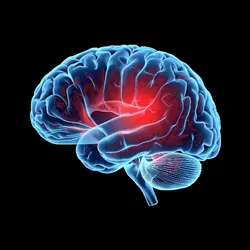

Reasons Behind Squint

The exact causes of squint are not always clear. However, a small percentage of cases can be linked to certain contributing factors –

Cerebral plasy

Hydrocephalus

Brain Tumours

Stroke

Head Injuries

Neurological problems